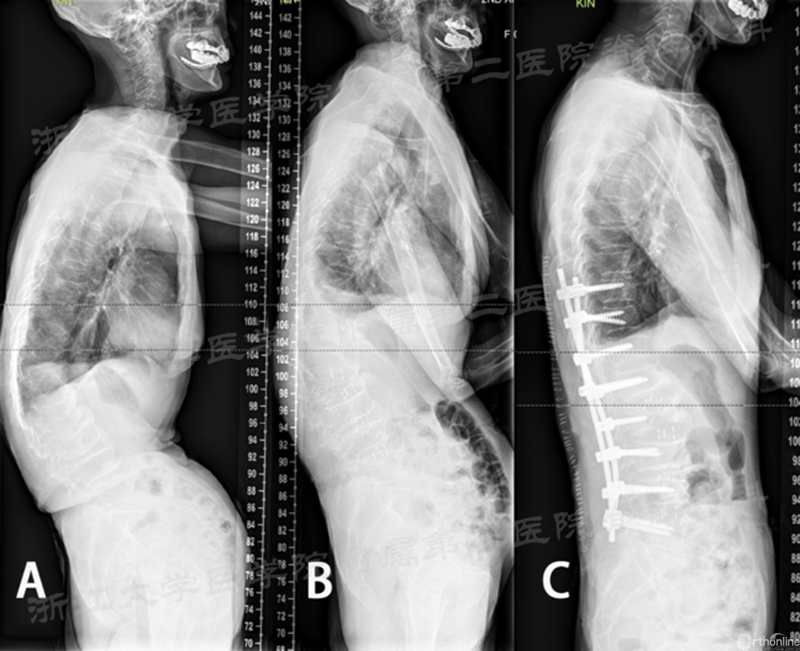

近期该团队对退行性脊柱侧凸患者手术的研究结果表明:采用CLIF技术结合II期再次评估,能获得良好的脊柱的矢状面和冠状面矫正,并为缩短侧凸患者的固定节段奠定基础。初期的临床结果显示,部分患者能有效地减少手术固定节段,这为减少手术创伤,减少手术并发症且保留腰椎的活动度提供了良好的保障,值得进一步的研究。

A.手术前;B.I期CLIF手术后;C.II期后路固定术后